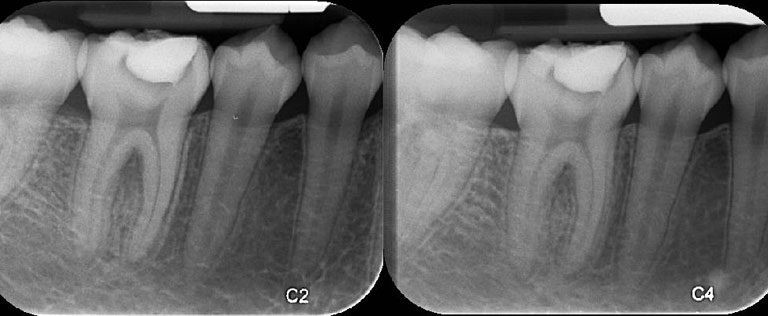

بالحديث عن كيفية تسكين الم الضرس ، فعادة ما يتم تشخيص التهاب لب السن من قبل طبيب الأسنان، حيث سيقوم طبيب أسنانك بفحص أسنانك، وقد يأخذ صورة أو أكثر من الأشعة السينية لتحديد مدى تسوس الأسنان والتهابها.ويمكن إجراء اختبار الحساسية لمعرفة ما إذا كنت تعاني من الألم أو عدم الراحة عند ملامسة السن للحرارة أو البرودة أو المنبهات الحلوة، يمكن أن يساعد مدى ومدة رد فعلك تجاه المحفزات طبيب أسنانك على تحديد ما إذا كان اللب قد تأثر بالكامل أو جزء منه فقط.يمكن أن يساعد اختبار الأسنان الإضافي، والذي يستخدم الطبيب أداة خفيفة الوزن، وغير حادة للنقر بلطف على السن المصاب، يساعد ذلك طبيب أسنانك في تحديد مدى الالتهاب.[1]